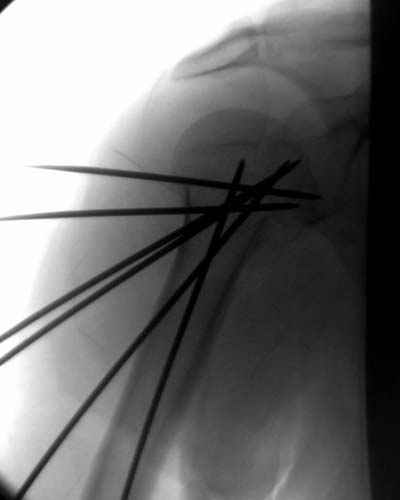

сделать закрытую репозицию с помощью ЭОПа совсем не сложно, после этого еще проще провести 3-6 спиц и получить красивую рентгенограмму. Есть только небольшая проблема это ROTATOR CUFF. Для плечевого сустава только костное восстановление не достаточно. для функции плечевого сустава нужны вращатели.

Давайте представим себе состояние манжетки вращателей после вывиха плеча, а еще и с отрывным переломом бугров. Головка может и прирастет, еесли не будет аваскулярного некроза, но хорошего функционального результата не ждите.

Висеть будет красиво. У людей физически активного периода жизни нужно открыть, восстановить костную анатомию и восстановить сухожильный аппарат.

В этом плане Locking plate очень хороша так как позволяет начать движения сразу после операции.

Клинические снимки - 3 недели после операции

с уважением М. Беренштейн